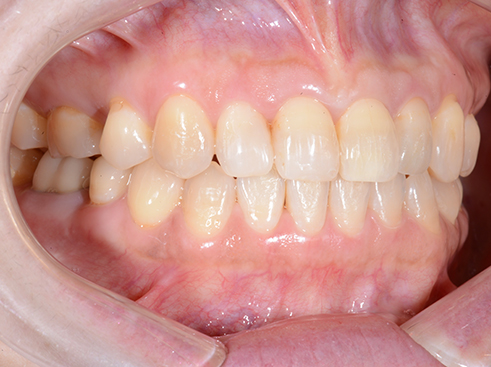

<受け口を治療した症例>

治療前

治療後